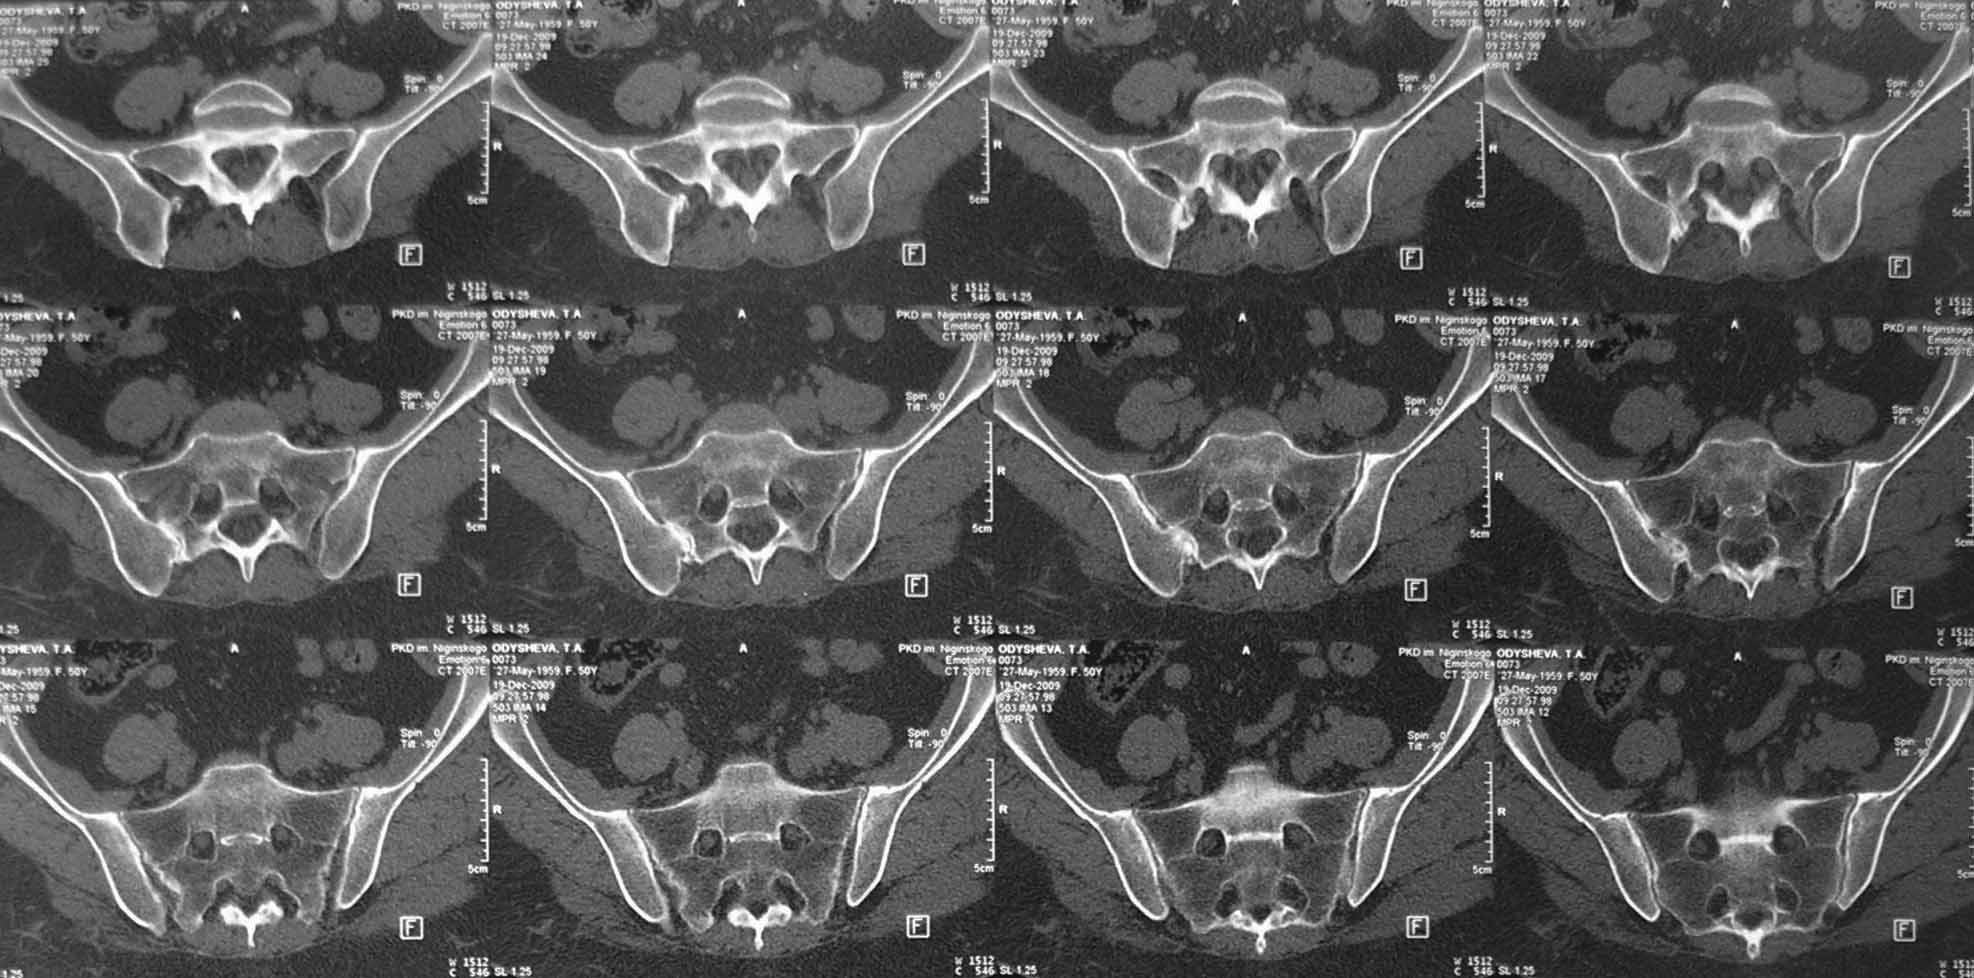

В 2009г установлен диагноз - сакроилеит справа.На представленных КТ имеется гипертрофия заднего отдела правой подвздошной кости с образованием контакта с задней поверхностью крестца.В январе 2011 года выполнена попытка удаления гипертрофированного участка подвздошной кости. удаленные участки кости исследованы гистологически - губчатая кость с элементами гиалинового хряща. После операции положительного эффекта не получено. На контрольной КТ от 04.2011 обнаружено что, желаемого результата операции не получено(интересующий участок удален частично), при этом имеется расслоение заднего отдела правой подвздошной кости.

На первичных КТ от 19-12-2009 определяется частичное анкилозирование правого крестцово-подвздошного сочленения, а на последних, от 11-04-2011 протяженность анкилозированной зоны значительно больше - сакроилеит прогрессирует, (с левой стороны вроде тоже признаки сакроилеита появились - не очень понятно из-за качества снимка). Значимых дуральных и радикулярных конфликтов действительно нет. "расслоение кости" - рентгенологически выглядит как травматический перелом подвздошной кости. Что делать? - наверное, искать серонегативные спондилоартропатии у ревматолога.